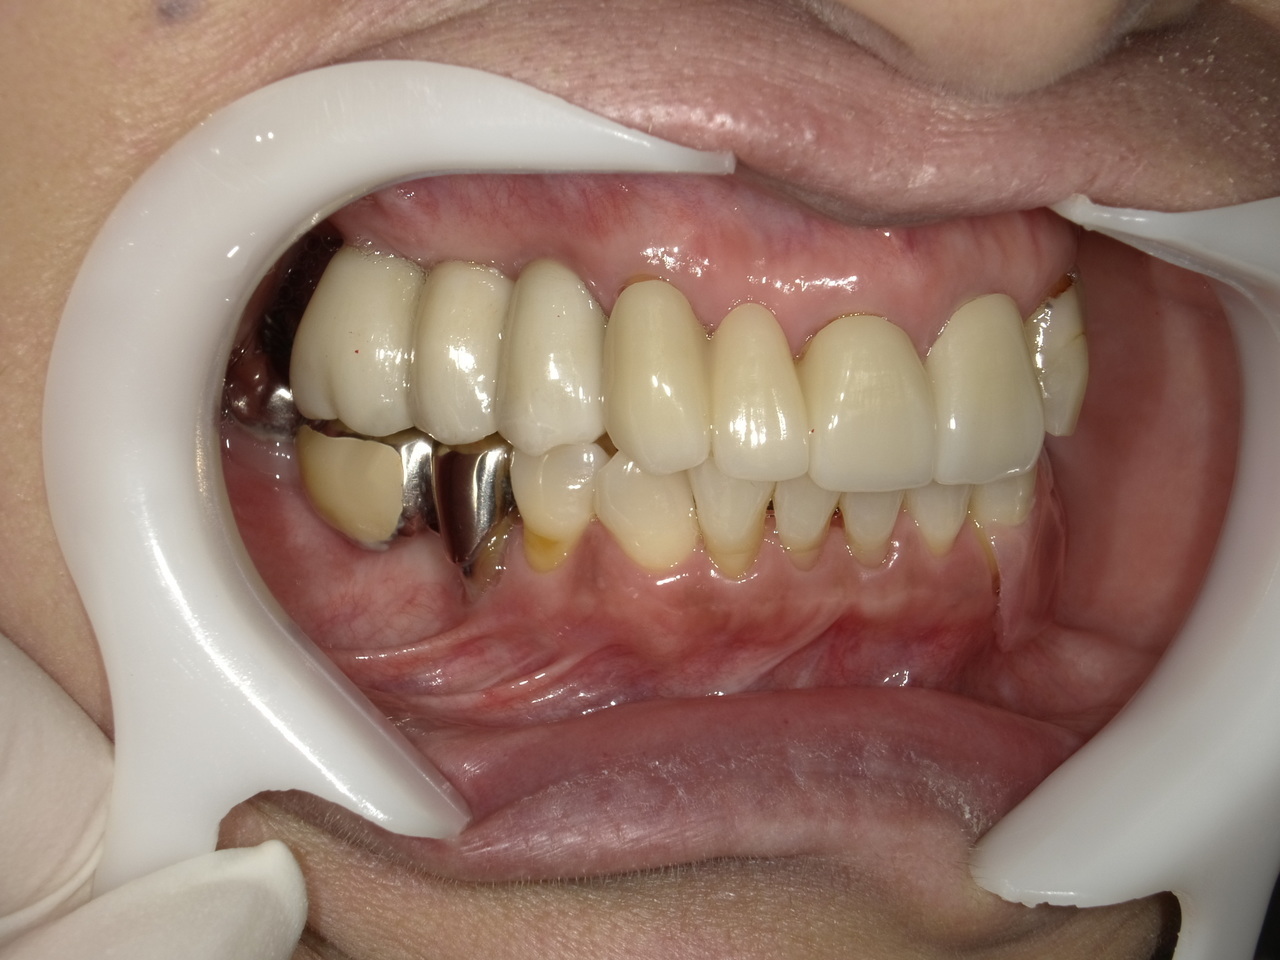

3.右上4番の著しい根露出と歯の周囲の骨の大きな欠損を伴った症例を2か月半で治療を終えたケース

Before

枚方市のインプラントの症例

After

M様 60代女性

症状としては、右上4番の根露出による動揺と疼痛がありました。

治療法としては、炎症が強いため、抜歯を行いました。その後、インプラント治療を希望されたため、インプラント埋入と、骨欠損部に人口骨を填入して、骨欠損部と歯肉の欠損部の回復を試みました。2か月後、歯肉の回復とインプラントの安定をみとめたため、デジタルにて印象を行い、2か月半後にインプラント上部ジルコニアを装着して治療を終えました。

治療結果としては、大幅な歯肉・骨欠損があったが、2か月半という短い期間での治療を完了することができ、かつ、十分な、歯肉も回復したため、ブラッシングしやすい環境を付与することができたため、インプラント周囲炎のリスクを軽減することができると考えます。

治療の期間・回数:約2.5か月、6回

治療の価格:352000円(税込)

治療費の内訳:インプラント基本料(フィックスチャー(メガジェン AnyOne使用)及び手術費用、投薬費用、レントゲン費用、インプラント上部費用(アバットメントおよびジルコニアクラウンの費用用)330000円(税込み)。人工骨費用 22000円(税込み)

治療のリスクや副作用:手術後に、痛みや腫れ、出血、合併症などを引き起こす可能性があります。噛む感覚がご自身の歯と異なる場合があります。見た目がご自身の歯と異なる場合があります。手術後にメインテナンスを継続しないと、インプラントが抜け落ちる可能性があります。